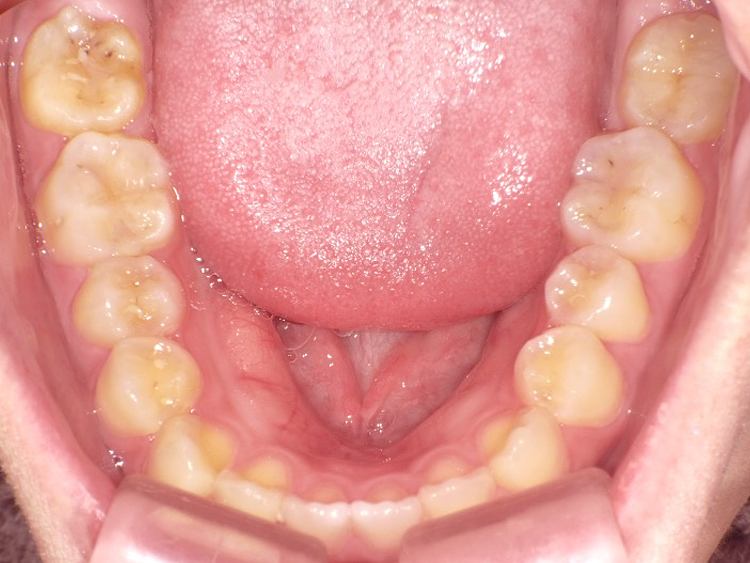

症例3

Before

After

| 主訴 | 上下の歯のガタガタを治したい |

|---|---|

| 年齢 | --- |

| 治療 期間 |

約10ヶ月 |

| 治療 内容 |

インビザラインiGoで上下顎の治療。 狭まっていた歯並びを広げることで、 ガタガタに並んでいた歯を綺麗に並べた。 |

| 治療費 | ¥517,000(税込)+月額調整料 |

| 治療のリスク | 歯と歯の間を削ることでスペースを確保するので、 場合によっては歯が染みる症状が出ることがある。 |